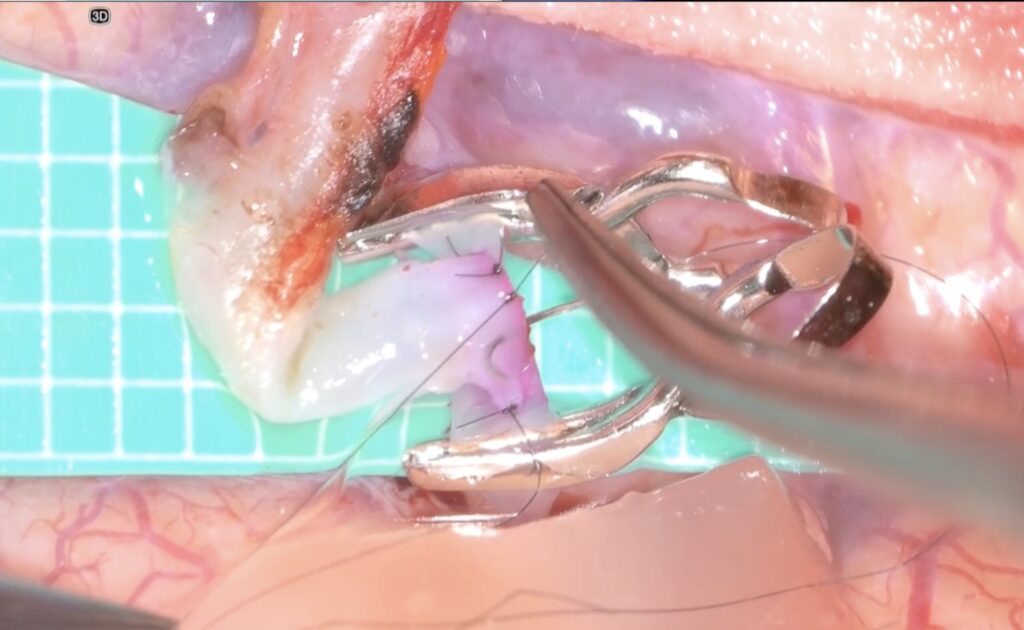

そして糸を結びます

次の針はまち針のように通してあり、しかも糸は常に繋がっていますので、針は無くなりません(Needle parking mehtod)